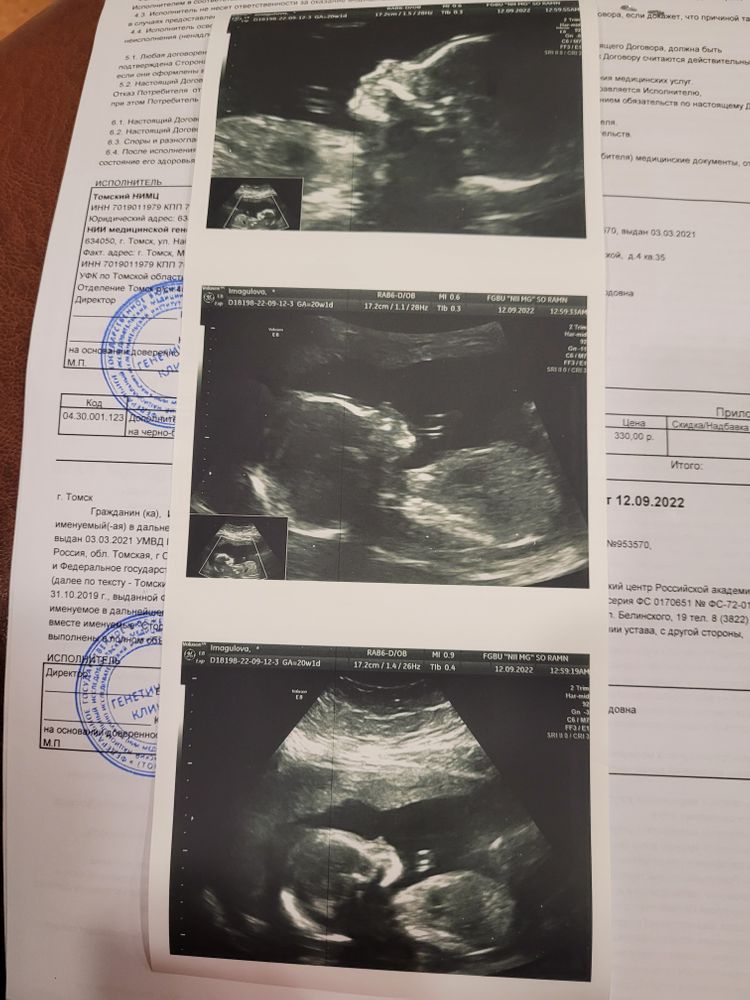

Но поставили свой диагноз. Левостороний плевральный выпот. Жидкость в левой груди. Легкое сжато из за жидкости,а сердце смешено в право из за того что давит легкое.Ребенок развивается по срокам. Отклонений других нет

Пришла 20 неделя вчера. У меня второй скрининг. И смотрят динамику.

И через 3 минуты она говорит "хочу поздравить вас ,у вас все рассасалось"

Легкое расправилось. Сердце встало на место. Сердце не измененно.

Ребёнок без потологий. Здоровый богатырь.380 гр